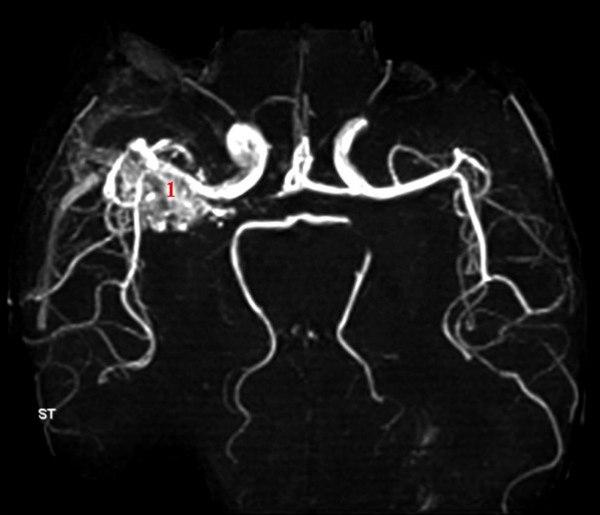

AV-malformasjon

AV-malformasjon (MR angio)

MR angio uten kontrast viser blodårenøste (1)